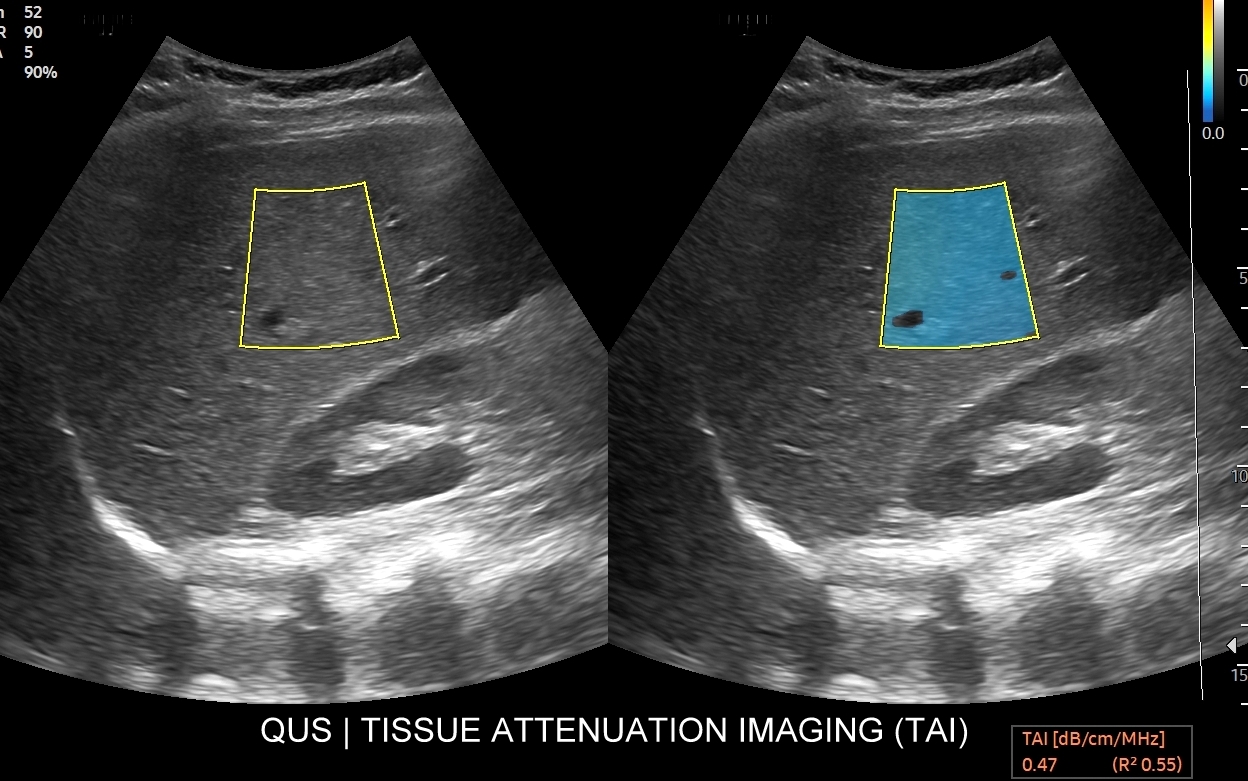

W ramach kompleksowej oceny wątroby elastografię 2D-SWE warto jednoczasowo połączyć z przeprowadzeniem badania USG przepływów wątrobowych oraz oceną stłuszczenia wątroby QUS w ramach kompleksowego badania MPUS brzucha. Podczas rejestracji zapytaj się o Multiparametryczne badanie USG / MPUS jamy brzusznej >